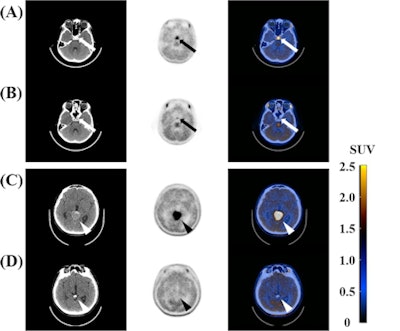

Clinical characteristics, imaging findings, and tumor markers such as α-fetoprotein (AFP) and beta-human chorionic gonadotropin (HCG) in serum and cerebrospinal fluid were used as clinical variables. Maximum standardized uptake value (SUVmax), tumor-to-normal tissue (T/N) ratio, and visual scoring of tumor were used as C-11 MET-PET/CT parameters.

All of the intracranial germinomas were well visualized on C-11 MET-PET/CT and the SUVmax of intracranial germinomas was higher than that of intracranial nongerminomas (p = 0.005), according to the findings.

Nonetheless, C-11 MET-PET/CT appears to have diagnostic value in patients with intracranial germinomas, with C-11 MET avidity as a potential surrogate biomarker of HCG, a standard clinical diagnostic marker for the tumors, they wrote.